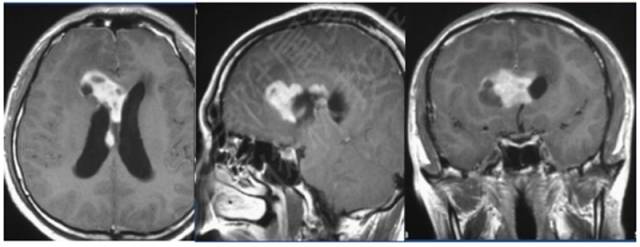

病例:男性,30岁,头痛2月

MR增强

病理结果:富于淋巴浆细胞型脑膜瘤,WHO I级

2、CT密度较高,钙化少见。MR T1信号等或稍低、T2信号稍低或稍高,增强后呈明显强化;病灶内或边缘可见T1低信号、T2高信号区,增强后不强化;病灶边缘可见广泛增厚的脑膜强化。肿瘤界限模糊,似炎症,累及皮层,瘤周水肿明显(特征性表现)。

3、此亚型脑膜瘤有丰富的慢性炎细胞浸润,易伴发造血组织异常。病理上以上皮细胞增生伴大量淋巴细胞、浆细胞浸润为特点。